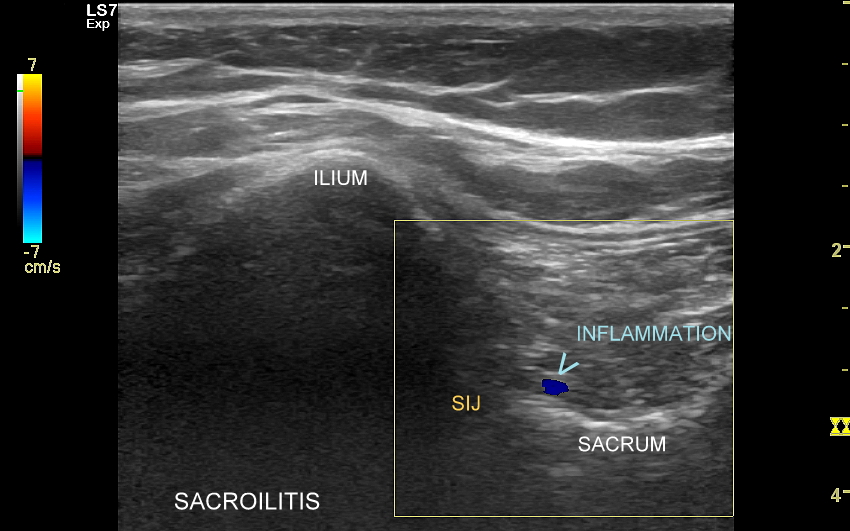

USG ma istotne choć ograniczone znaczenie w diagnostyce stawu biodrowego. U niemowląt używane jest przede wszystkim w ramach profilaktyki preluksacyjnej, a u dzieci starszych w celu oceny urazów sportowych i zapaleń (np. odczynowych). U dorosłych z kolei USG okolicy biodra wykorzystywane jest przy wykrywaniu stanów zapalnych, wysięku w stawie biodrowym, zmian zwyrodnieniowych, niektórych urazów w samym stawie (np. urazy obrąbka stawowego), a także patologii w sąsiedztwie, takich jak tendonopatie, zapalenia kaletek, zespół bólowy okolicy krętarza większego, uszkodzenia i naderwania mięśni okolicy biodra, krocza oraz pachwiny, uszkodzenie Morela-Lavallée’a, przeskakujące pasmo-biodrowo-piszczelowe, przepukliny pachwinowe i udowe, neuropatie, limfadenopatie, tętniaki, a także inne.